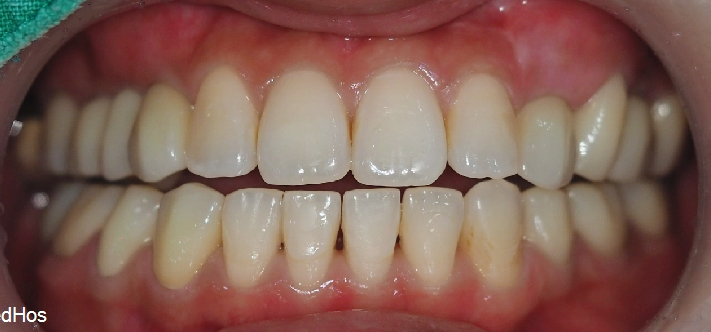

위의 사진이 최종 치료 사진 입니다. 뼈이식, 신경치료 후 크라운, 임플란트 치료를 진행 하였고

▲ 최종 완료 구강 사진

환자분은 대면이 많은 직업이라 매우 신경이 쓰이셨는데

지금은 너무 만족 하신다고 매번 관리 기간때마다 말씀 해주셔서

저희도 뿌듯할 따름 입니다.